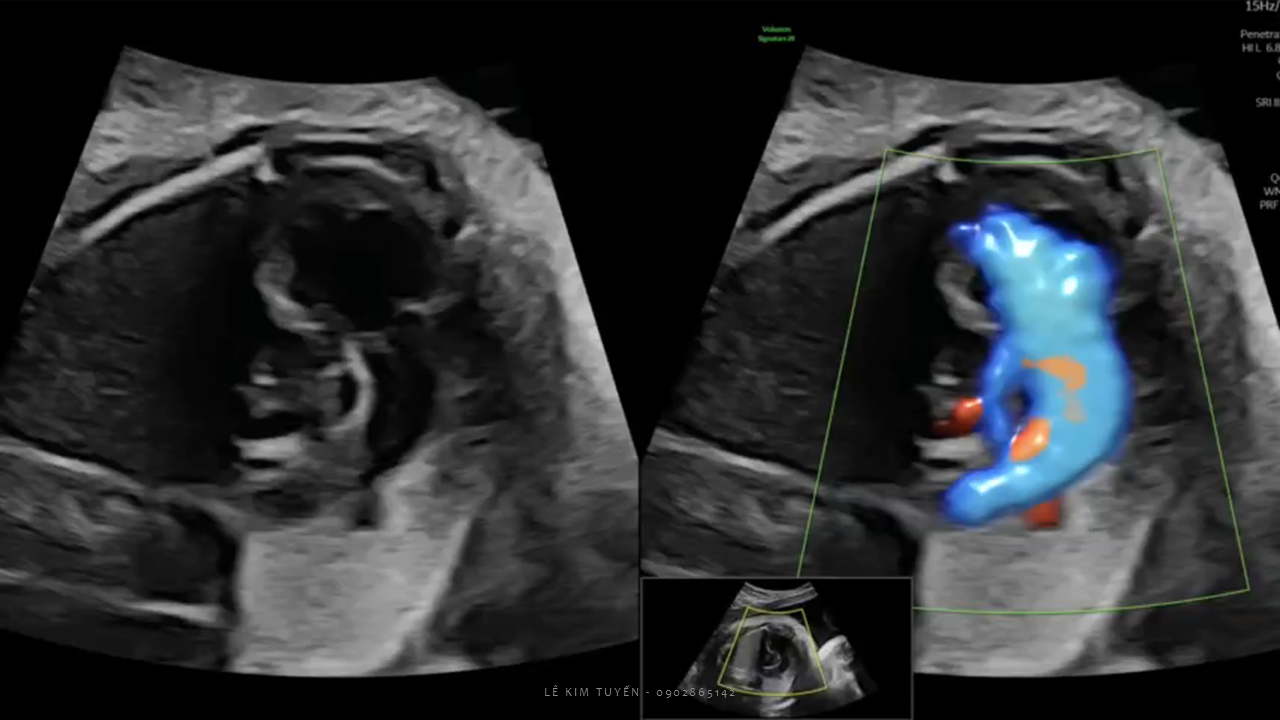

Siêu âm tim thai - Các kỹ thuật hiện đại

TS. BS. Lê Kim Tuyến

Bệnh viện Tim Tâm Đức